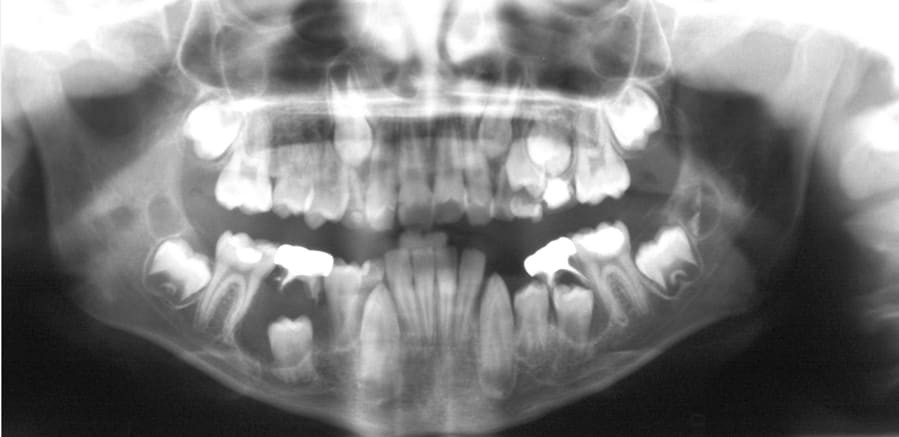

What is a dentigerous cyst?

Dentigerous cysts are the second most common type of odontogenic cyst, which is a fluid-filled sac that develops in the jaw bone and soft tissue. They form over the top of an unerupted tooth, or partially erupted tooth, usually one of your molars or canines. While dentigerous cysts are benign, they can lead to complications, such as infection, if left untreated.

What are the symptoms?

Smaller dentigerous cysts might not cause any symptoms. However, if the cyst grows larger than 2 centimeters in diameter, you may notice:

swelling

tooth sensitivity

tooth displacement

If you look inside your mouth, you may also notice a small bump. If the cyst causes tooth displacement, you might also see gaps slowly forming between your teeth.

What causes it?

Dentigerous cysts are caused by a buildup of fluid over the top of an unerupted tooth. The exact cause of this buildup is unknown.

While anyone can develop a dentigerous cyst, they’re more commonTrusted Source in people who are in their 20s or 30s.

How is it diagnosed?

Small dentigerous cysts often go unnoticed until you have a dental X-ray. If your dentist notices an unusual spot on your dental X-ray, they may use a CT scan or MRI scan to make sure it’s not another type of cyst, such as a periapical cyst or an aneurysmal bone cyst.

In some cases, including when the cyst is larger, your dentist may be able to diagnose a dentigerous cyst just by looking at it.